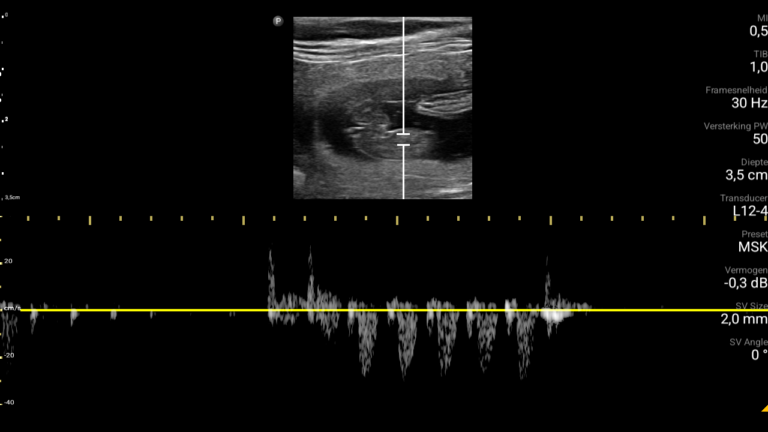

Op 3 mei 2024 was het dan eindelijk zover, de dag van de echo. Bij de echo zagen we meteen het eerste pupje en wisten we gelijk, ZE IS DRACHTIG! Wat was het bijzonder om de kleine pupjes te zien en de hartslagjes te horen.

Echo dag 32